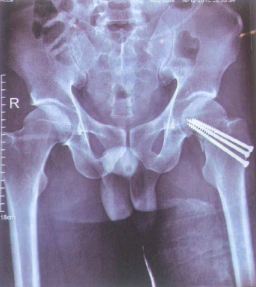

Hình 4.19. Hình ảnh X-quang sau mổ kết hợp xương vít xốp cổ xương đùi trái

Sau khi mổ kết hợp xương vùng cổ xương đùi vững, việc vận động chủ động và thụ động biên độ khớp háng được bắt đẩu sớm nhất có thể để tránh biến chứng cứng khớp.

Khi ổ gãy chưa có dấu hiệu liền, việc tỳ đè được khuyến cáo sau 6-8 tuần sau phẫu thuật.